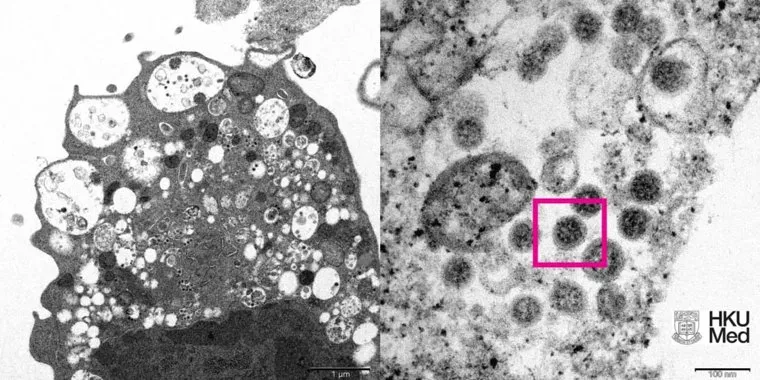

Китайский медицинский институт HKU Medicine опубликовал первые фотографии нового штамма коронавируса «Омикрон». Фотографии показывают поврежденные клетки с набухшими везикулами, содержащие мелкие черные вирусные частицы.

«Это увеличение электронной микрофотографии клетки почки обезьяны (Vero E6) после заражения вариантом SARS-CoV-2 Omicron. Электронная микрофотография инфицированной клетки Vero E6 с большим увеличением показывает агрегаты вирусных частиц», — сообщается на официальном сайте института.